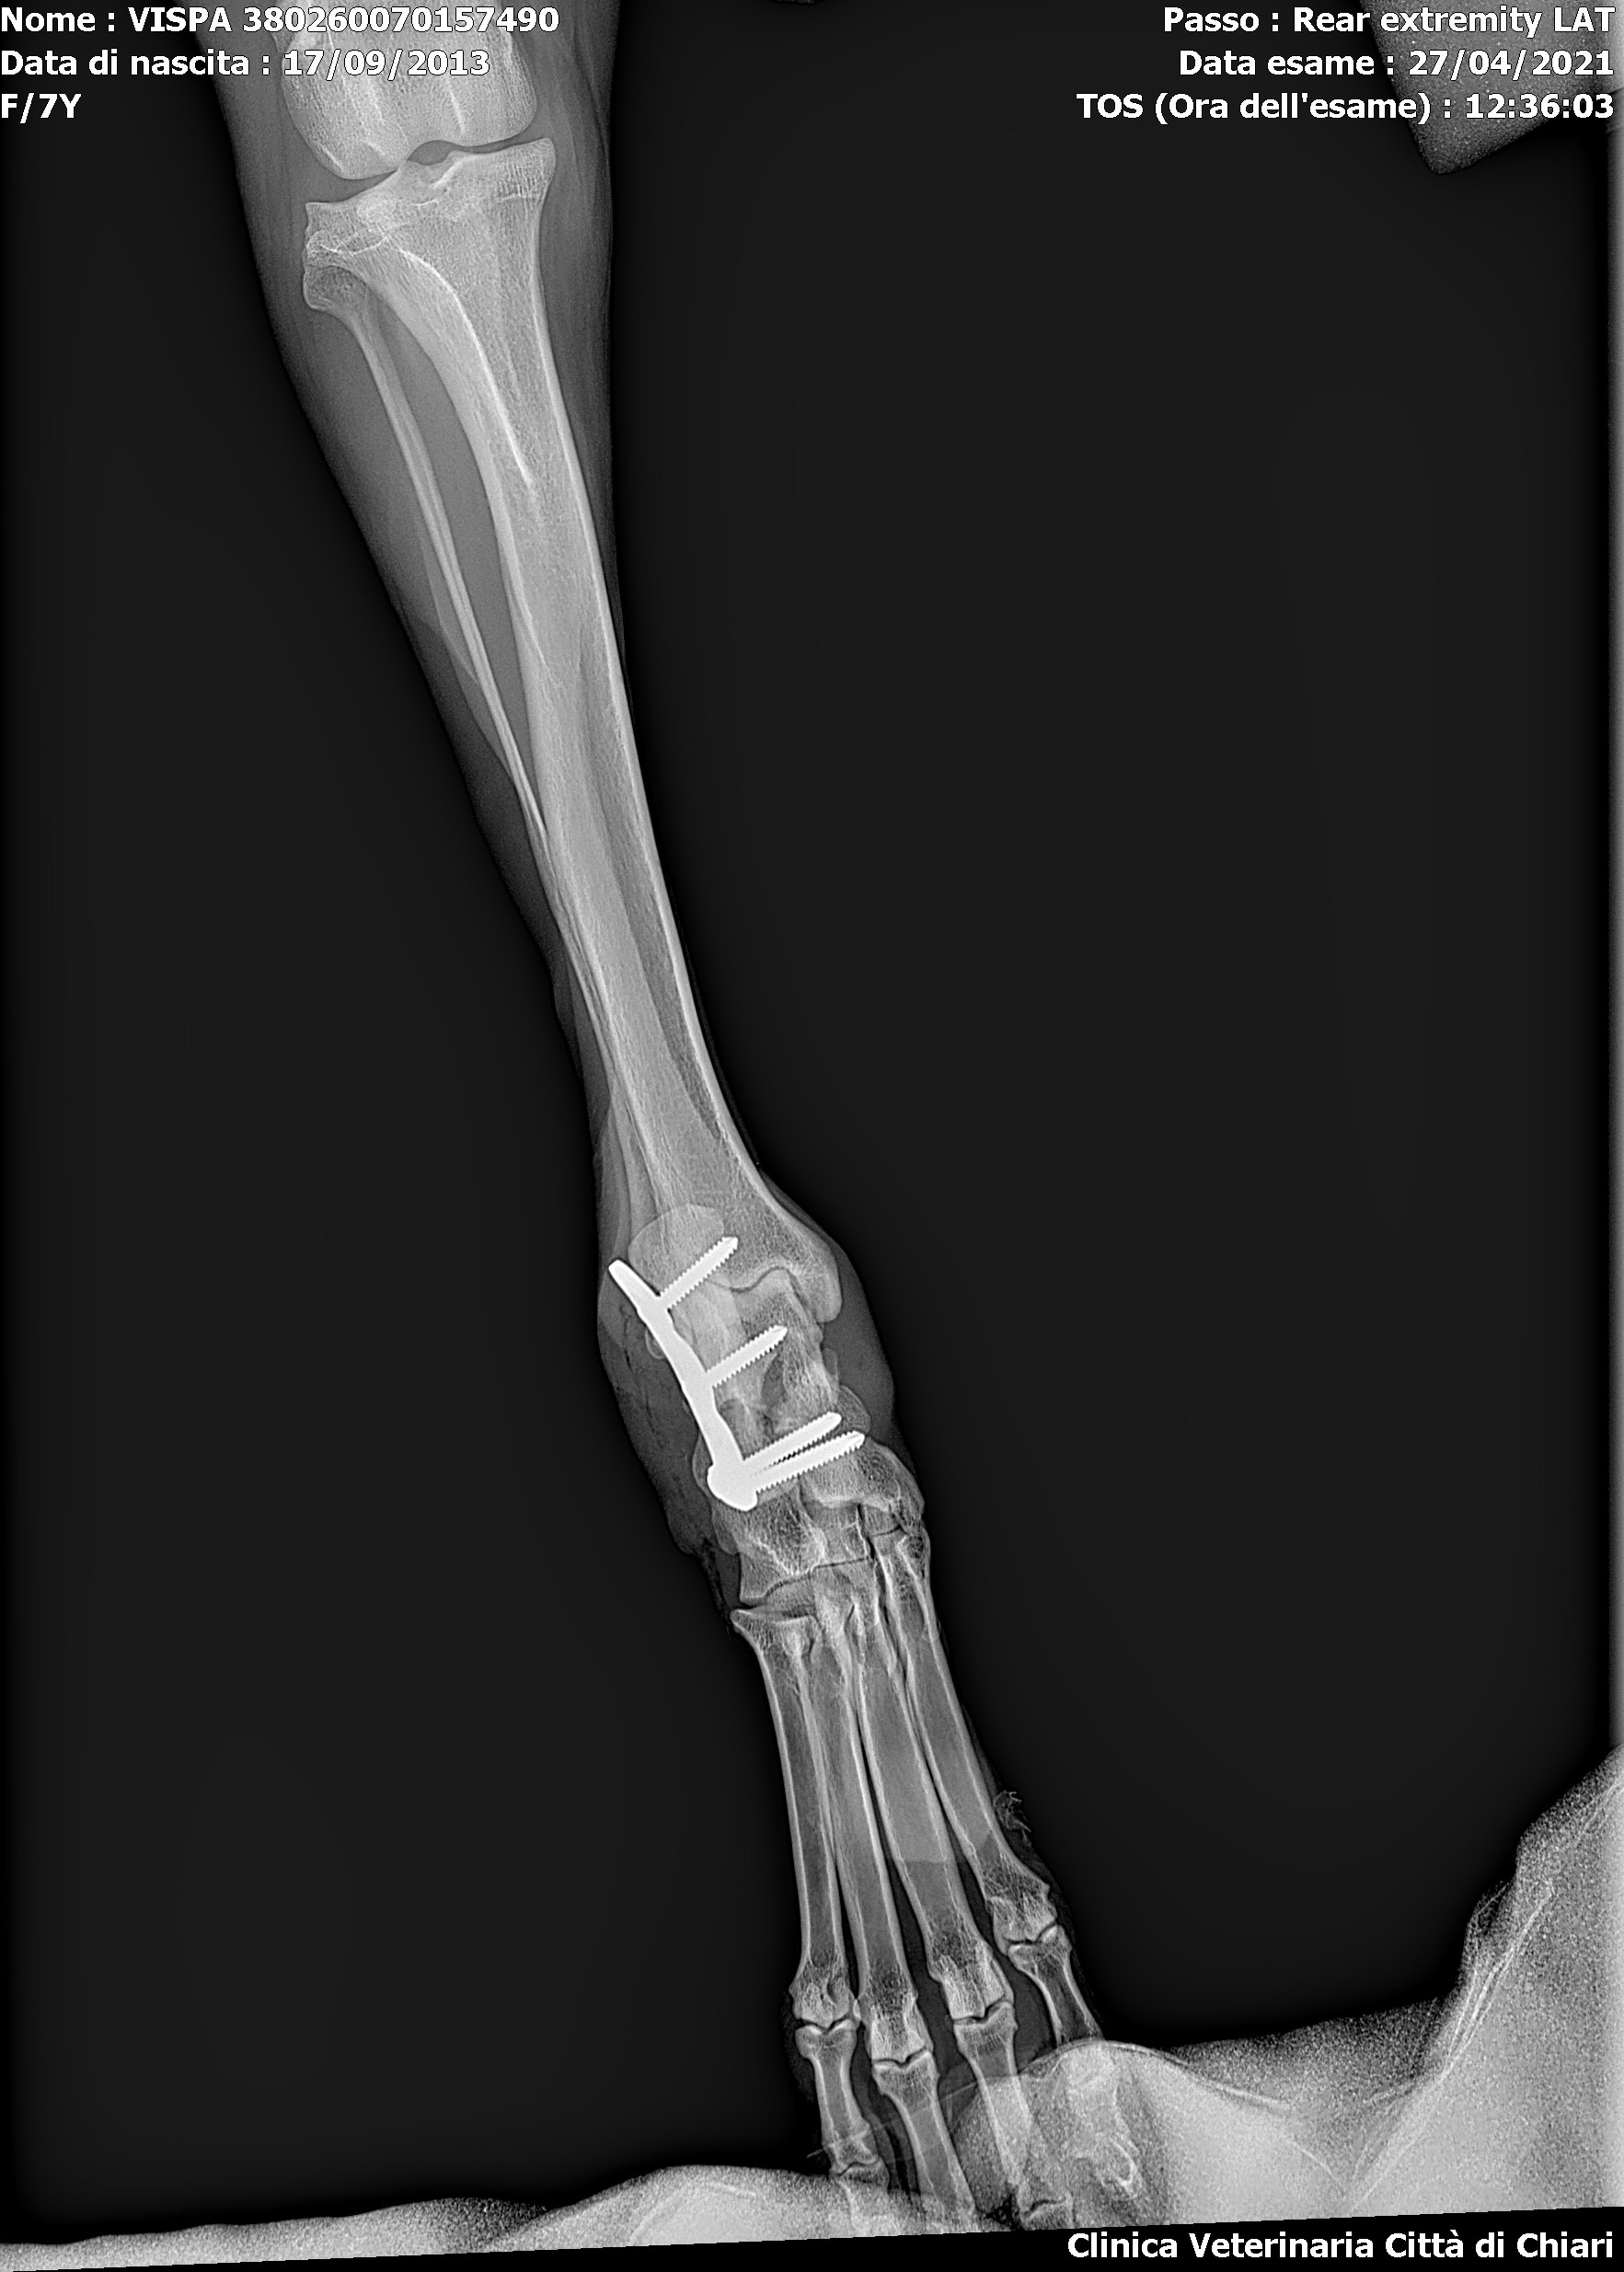

Osteosintesi del Calcaneo